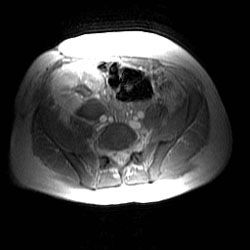

RADIOLOGY: KIDNEY: Case# 33985: PTLD. Renal transplant patient. 1) Echogenic mass with cystic component in the renal transplant hila causing focal stenosis in the main renal artery. The appearance would be most consistent with post-transplant lymphoproliferative disorder. Alternatively, renal abscess in this area cannot be excluded. Correlation with clinical history recommended. 2) Marked hydronephrosis with internal debris within the collecting system of the transplant kidney. This is felt to likely be due to obstruction from the above mass. 3) Small bilateral pleural effusions and small amount of ascites.